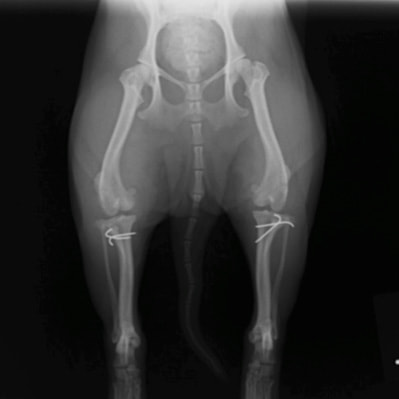

■ 症例24 キャバリア 7か月

左右膝蓋骨内方脱臼(左:グレードⅣ 右:グレードⅢ)

以前から左右後肢の跛行が認められ、整形外科学的検査・レントゲン検査により左右の膝蓋骨脱臼が認められた。症状が重度である左膝の膝蓋骨脱臼整復術を行った。外科手技は縫工筋及び内側広筋の解放、脛骨粗面の外側転位、滑車ブロック形造溝術、内外側関節方の縫縮を実施した。術後一か月時点で、左の膝蓋骨は安定しており経過は良好である。

本症例は成長期における重度の膝蓋骨脱臼であり、術後の再発の可能性もあるため、経過をしっかりと観察していく必要がある。また、今回手術を実施していない右膝に関しても経過を観察し、手術を検討していくこととする。